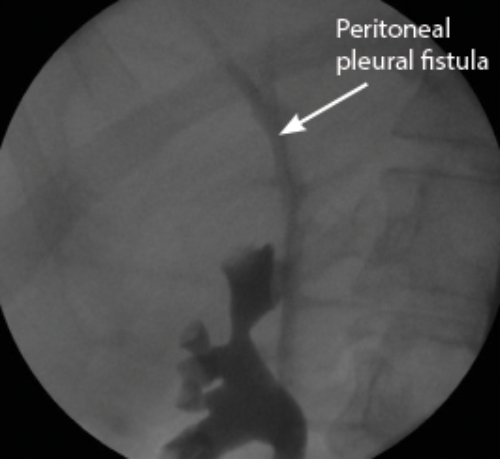

A 45-year-old woman was admitted under the care of the medical team with shortness of breath, renal failure and abdominal distension six weeks post laparoscopic hysterectomy. A small right-sided pleural effusion was present on chest x-ray and large-volume ascites was identified on ultrasound. Drainage of both the chest and the abdomen confirmed the fluid to be urine.

Bilateral retrograde studies revealed extravasation of contrast from the distal left ureter with the contrast seen travelling in a peritoneal pleural fistula on the right retrograde (Figure1.). After a failed attempt at inserting a left ureteric stent due to complete transection and retraction of the ureter a nephrostomy successfully diverted the urine leak. A Boari flap ureteroneocystostomy was performed via a lower midline incision with a covering ureteric stent six weeks later. A MAG3 scan was performed six weeks after the ureteric stent had been removed which showed equal split function with good drainage bilaterally.